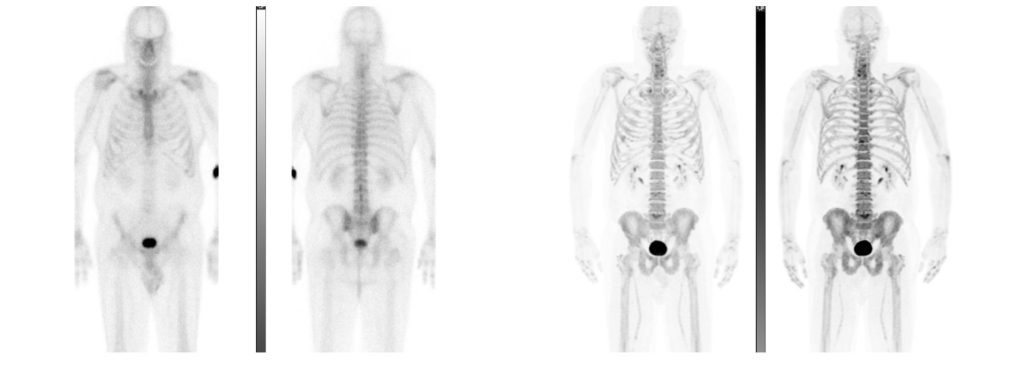

Effectivement, en plus de procéder par scintigraphie osseuse (examen où les patient.e.s ingèrent un produit légèrement radioactif afin qu’une caméra décèle les anomalies révélées par les radiations), l’équipe réalise aussi de la tomographie par émission de positons (TEP) au fluorure de sodium (NaF).

Il s’agit d’un processus ayant des retombées similaires, mais qui emploie un type de caméra TEP, appareil qui était déjà en fonction à Laval.

L’avancée technologique permet de détecter les métastases osseuses en quelques minutes alors que la précédente façon de faire sollicitait une heure de travail. De plus, le temps passé à l’hôpital qui était d’environ cinq heures a diminué à une heure et demie.